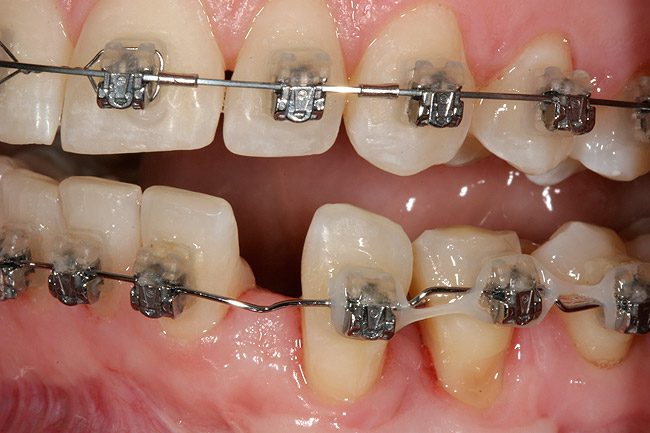

This treatment plan was elected with the premise to reevaluate treatment options during orthodontic tooth movement. Soft-tissue augmentation was initiated to correct the mucogingival defect in the area of teeth Nos. 21 and 22. A free gingival graft was performed to achieve an adequate band of attached and keratinized gingiva to resist potential stripping on the root surfaces of teeth Nos. 22 and 21 during orthodontic movement (Figure 8). Orthodontic movement then was initiated to site-develop position No. 23 for an implant (Figure 9 through Figure 11). Orthodontics also was used to idealize the patient’s occlusion and develop canine guidance to minimize occlusal load and maximize the redistribution of forces36-40 for protecting the future implant from deleterious forces. The space was opened around the peg lateral tooth No. 7, and the gingival levels were aligned for maxillary incisors. Bonding was performed to restore the length of teeth Nos. 8 through 10 and to bond the peg lateral to a normal tooth form, which allows the orthodontist to idealize the posterior occlusal scene and maintain canine guidance (Figure 12 through Figure 13).

Following the first goal of orthodontia—moving tooth No. 22 to a proper functional and anatomical position—a periodontal reevaluation was performed, demonstrating an improvement in short- and long-term tooth prognosis. At this time, the decision was made to abort continual extrusion of teeth Nos. 21 and 22, although some attachment level discrepancy remained between Nos. 21 and 22 (Figure 14). Implant diagnostics ensued and included mounted study models and a diagnostic wax-up. A scanning appliance was created to demonstrate the desired prosthetic outcome requirements, and the patient was referred for computed tomography (CT) scans. CT scan assessment demonstrated successful orthodontically directed GBR to allow implant placement (Figure 15 through Figure 16). Only minor GBR therapy would be needed and could be accomplished simultaneously with implant installation. Guided implant placement occurred, using an open flap approach (Figure 17). During surgery, root dehiscences were noted on teeth Nos. 21, 22, 24, and 25, as well as the anticipated dehiscence following implant placement at No. 23 (Figure 18). A positioning reference (index) was secured after implant placement to facilitate a provisional prosthesis at stage II surgery. Cortical perforations then were placed adjacent to the implant to encourage angiogenesis (Figure 18), and mineralized freeze-dried bone allograft enhanced with platelet-derived growth factor was placed over the dehiscences for purposes of guided tissue regeneration and GBR (Figure 19). A highly resorbable collagen membrane was placed to stabilize the allograft. The flap was coronally repositioned, and primary-intention wound healing was achieved (Figure 20 and Figure 21). Following 4 months of stage I surgery, implant uncovery and immediate provisionalization were performed in conjunction with connective tissue grafting. Final orthodontic tooth movement then ensued, using the implant as anchorage to optimize end-tooth movements, interroot separation, and the cuspid-protected occlusal scheme. A final impression then was secured, and a zirconia abutment (Figure 22) with an all-ceramic restoration was fabricated for the prosthetic phase completion of No. 23 (Figure 23 through Figure 25).

Figure 12  Right buccal view showing posterior occlusion established, canine guidance and proper space appropriation around peg lateral tooth No. 7, and intruded worn incisors.

Figure 12